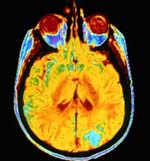

CAT Scan

A CAT (computer assisted tomography) scan is a cross-sectional image created by taking traditional x-ray images from many different directions and then using a computer to calculate the shapes and positions of objects blocking the x-rays. CAT scans were impossible before the availability of the modern computer. David Kuhl and Roy Edwards built a transmission CT scanner. Their CT scan of a patient on 14 May 1965 was possibly the first ever made. In the 1960s Allan Cormack in the United States did important work on a scanning method that projected gamma rays (which is electromagnetic radiation of shorter wavelength than x-rays) through an object on a rotating platform. In the early 1970s Godfrey Hounsfield in England developed a CT scanner and produced medical images. Within a few years there were hundreds of CAT scanners throughout the world, and in 1979 Cormack and Hounsfield shared the Nobel Prize in Medicine for their work in developing computer assisted tomography.